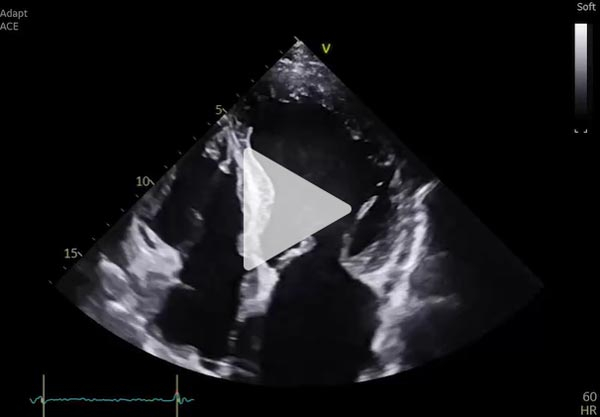

Une nouvelle réévaluation écho cardiographique

- VG dilaté (DTD 62 mm VTD 89 ml/m²) hypertrophie SIV 15 mm

- FEVG altérée 20% ,SLG altérée -15% avec un gradient base-apex >1 et septum basal-apical > 2,1

- IM modérée

- Décollement péricardique minime en regard du VG

Vidéo 10